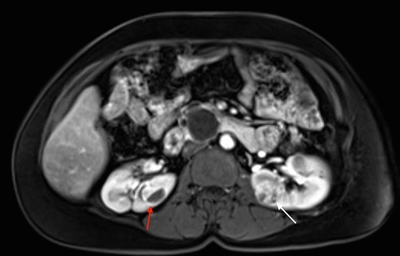

Manifestaciones renales

Más del 55 % de las personas con la enfermedad de Von Hippel-Lindau (VHL) solo presentan múltiples quistes de células renales. Los carcinomas de células renales (RCC) relacionados con la enfermedad de VHL suelen ser multifocales y bilaterales, y forman masas con componentes quísticos y sólidos.[1] En la enfermedad de VHL, se notificó un riesgo acumulado de RCC del 24 % al 45 %. Los RCC menores de 3 cm tienden a ser de grado bajo (grado nuclear de Fuhrman 2) y de invasión mínima.[2] Sin embargo, su tasa de crecimiento varía mucho.[3] En una investigación de 228 lesiones renales en 28 pacientes seguidos durante por lo menos 1 año, se observó que la transición de un quiste simple a una lesión sólida fue infrecuente.[1] Los quistes complejos y las lesiones sólidas contenían tejido neoplásico uniformemente extendido. Estos datos se pueden usar para predecir la progresión de las lesiones renales (de benignas a malignas) en pacientes con enfermedad de VHL. En la Figura 1 se observan tumores renales bilaterales en un paciente con enfermedad de VHL.

Vista de un corte transversal del cuerpo donde se observan tumores en ambos riñones. En el riñón izquierdo se ve un tumor con un componente quístico oscuro y en el riñón derecho se ve un tumor predominantemente sólido.

Es posible que los tumores de más de 3 cm aumenten de grado a medida que crecen y que produzcan metástasis.[3,4] Los RCC a menudo permanecen asintomáticos durante largos períodos de tiempo.